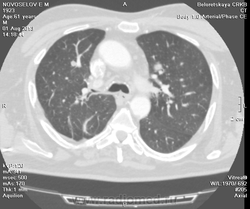

Метастазов в легкие не вижу. Похоже на лимфоузел в головке левого корня. Если позволите, запаздываете с началом исследования, плотность контраста в легочных артериях должна быть выше, чем а аорте. А одышка, не мудрено, легочная ткань диффузно уплотнена по типу "матового стекла", написал бы какую-нибудь интестициальную пневмонию, по типу альвеолита, может быть и гиперчуствительный пневмонит (не разберу есть или нет внутридольковые очажки), посмотреть бы изначально легочное окно, а не восстановленное из мягкотканного.

В диф. ряд: саркоидоз, атипичная форма.

Кажется,я понял,что Вы имели ввиду.Очажки стрелочкой указал.Согласен с тем,что очаги на фоне отображеничя сосудов кажутся фантазией,но они присутствуют.

Коллега, вынужден извинться и дезавуировать свой первый пост. Пересмотрел. Да, есть очаги, и они - вероятнее всего, метастазы.